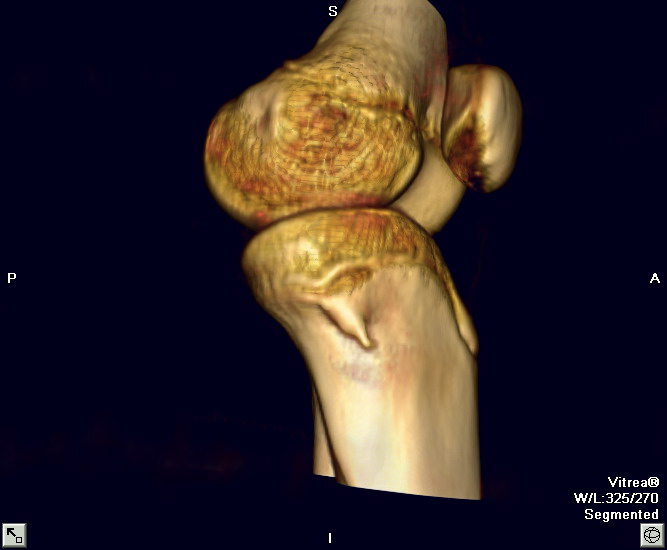

以下是引用zxl51642在2010-2-20 14:49:00的发言:[br]1)左胫骨近端干骺端外生骨疣,同意。[br]2)右胫骨纤维骨皮质缺损?不同意。[br]fcd无软组织肿块,是否可考虑软组织病变如骨膜软骨瘤、骨膜硬纤维瘤、神经纤维瘤之类的病变,给平片和ct轴位像。

以下是引用zxl51642在2010-2-20 14:49:00的发言:[br]1)左胫骨近端干骺端外生骨疣,同意。[br]2)右胫骨纤维骨皮质缺损?不同意。[br]fcd无软组织肿块,是否可考虑软组织病变如骨膜软骨瘤、骨膜硬纤维瘤、神经纤维瘤之类的病变,给平片和ct轴位像。